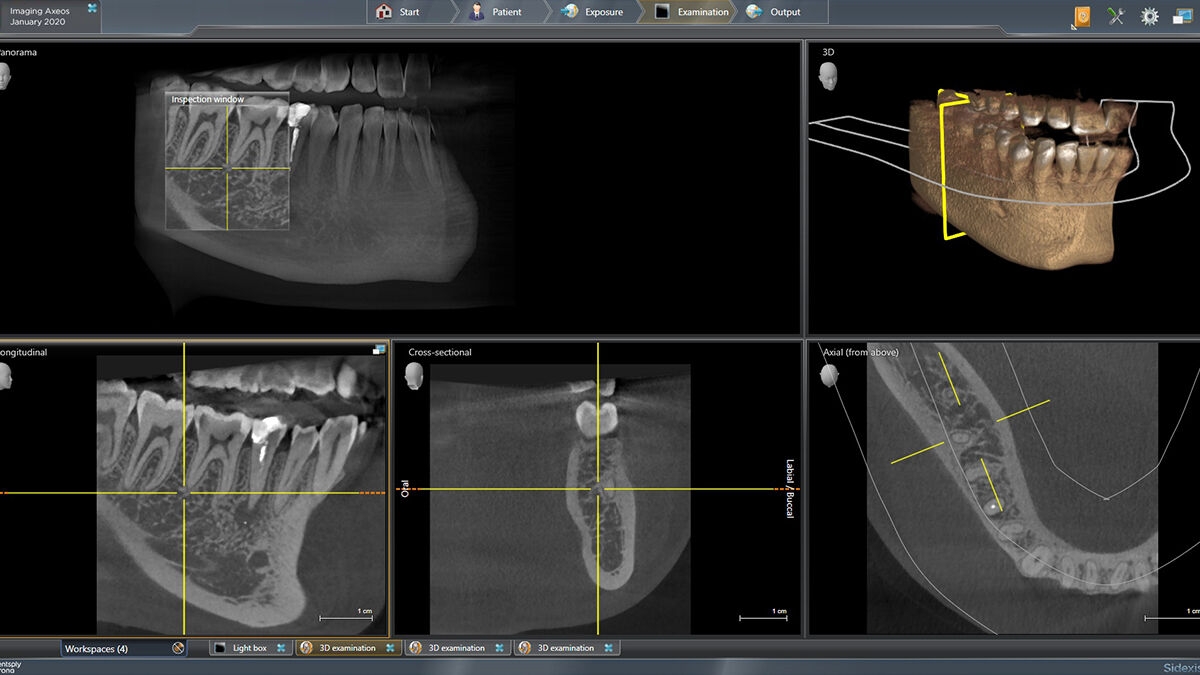

3D示例图